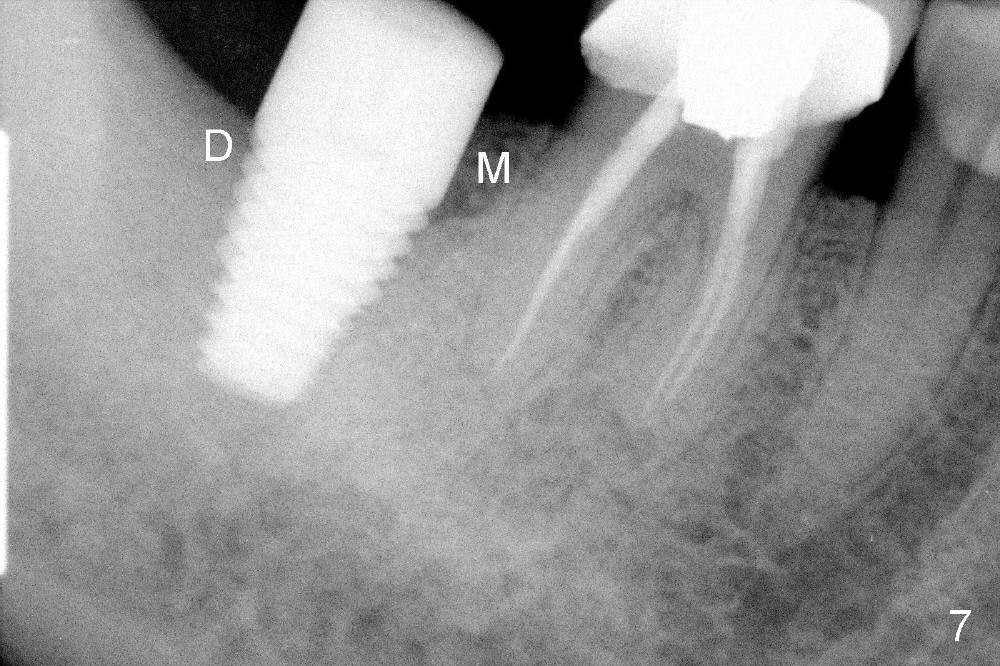

No. First at all, CT should be taken when 2D image does not show IAN. Fortunately, the surgery happens to be executed better than the plan. Clindamycin is used for socket soaking for 5 minutes. The initial osteotomy should be not exceeded 6 mm from the distal surface of the first molar (Fig.3: 5.92 mm). The 2 mm pilot drill (D) penetrates the mesial slope of the socket (red line) for 3-4 mm. There is 2.72 mm from IAN (yellow line: upper border of IAN canal). If the implant is placed along the long axis of the tooth, the initial osteotomy should start at the apex of the socket. The same pilot drill (black outline) penetrates the nascent bone for the same distance (3-4 mm) for primary stability, IAN may be invaded! The patient is a severe gagger. She manages to allow us to take this PA (Fig.3) and the next one (Fig.4 with 6x14 mm tap in place, primary stability having been achieved). To close the socket, a 7x14 mm implant is placed. Immediately postop PA is taken twice without success. The socket is closed with 2 sutures and heals around the implant 8 days postop (Fig.5,6). PA is taken 2 months postop (Fig.7). The implant is not placed as deep as planned. It is stable without paresthesia of the lower lip. An abutment is placed (Fig.8: A) nearly 3.5 months postop.